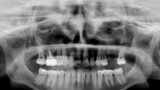

Fig. 14: Dental panoramic tomogram of initial situation.